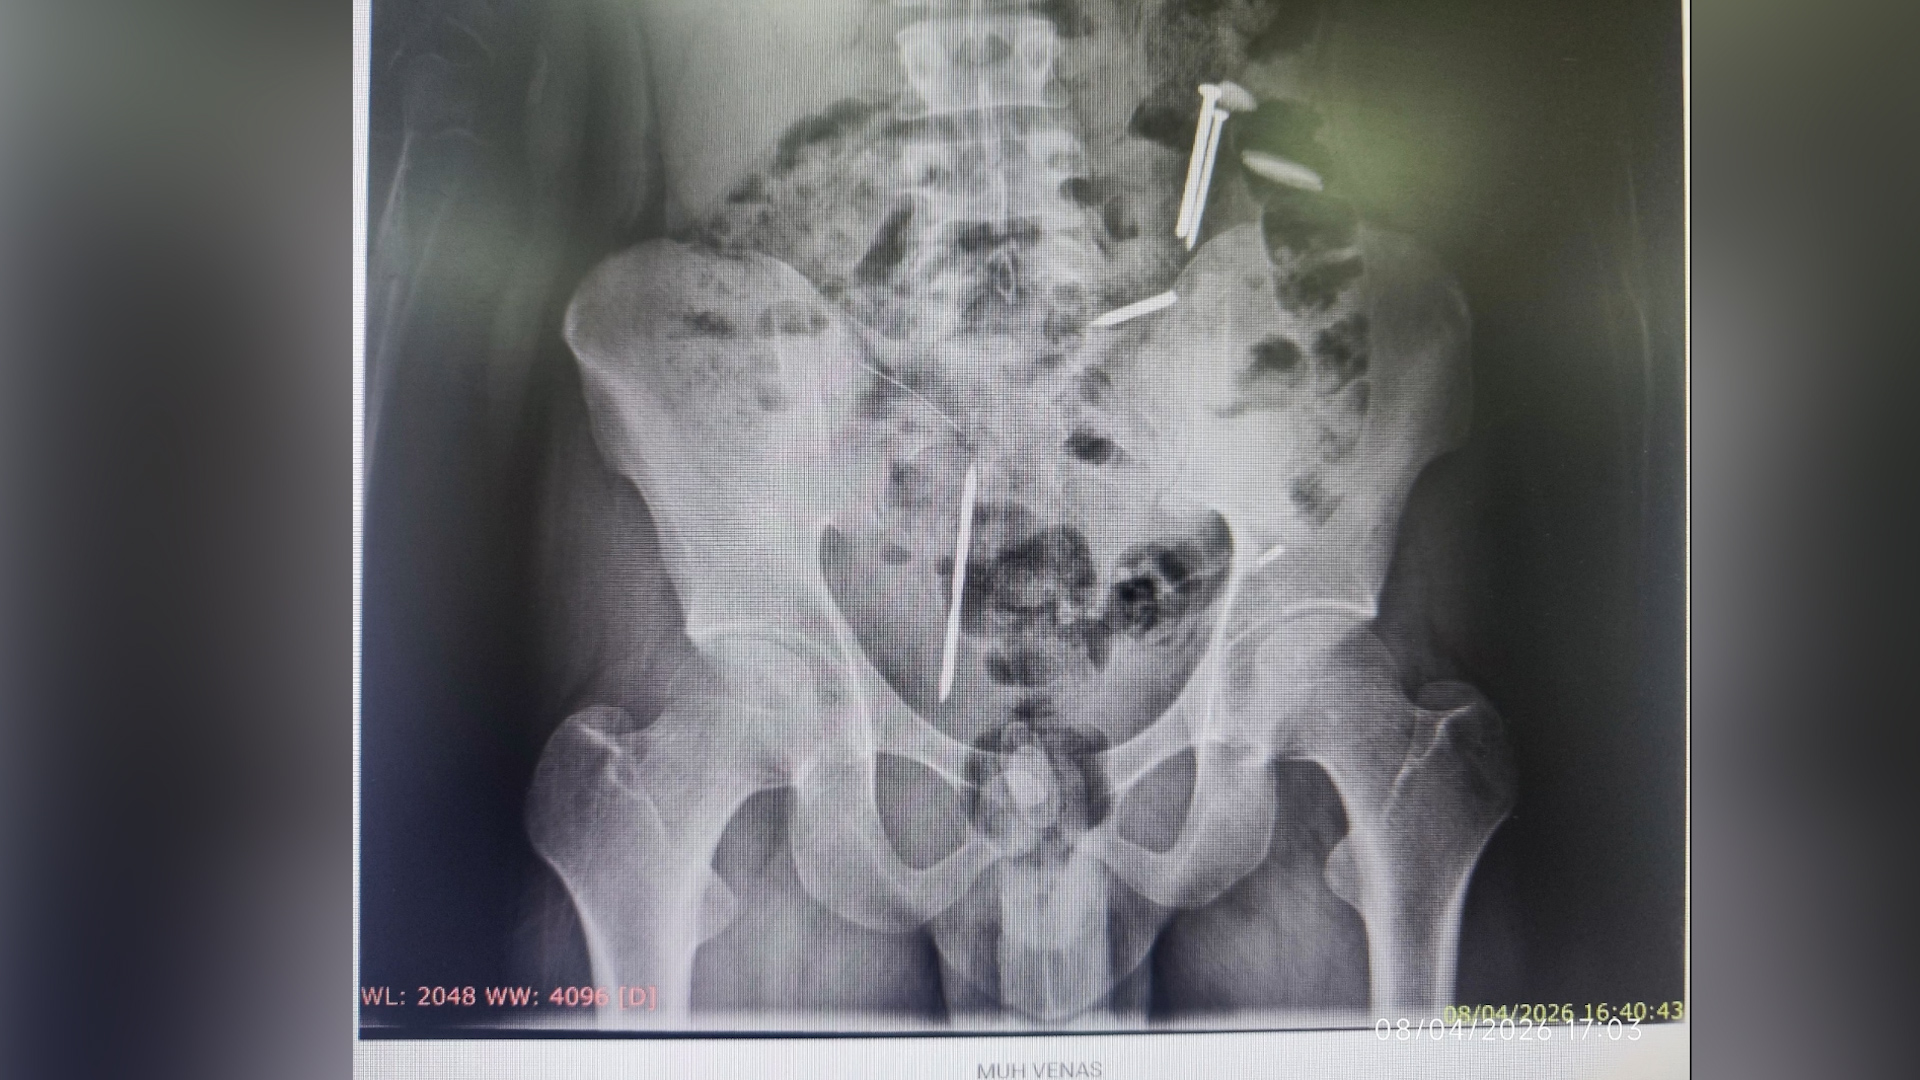

Sehari setelah evakuasi, MVA dirujuk ke RSJ Lawang untuk mendapatkan penanganan medis lebih lanjut. Hasil pemeriksaan rontgen mengungkap fakta mencengangkan: terdapat dua buah paku, dua keping koin, serta satu benda menyerupai kawat di dalam tubuhnya.

Keluarga mengaku tidak mengetahui keberadaan benda-benda tersebut. Mereka hanya mengetahui bahwa MVA kerap mengonsumsi benda-benda tidak lazim.